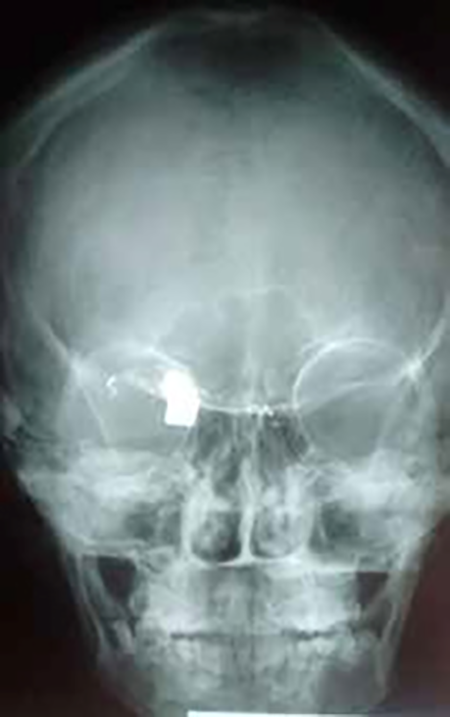

Figura 1

Caso 1

A.B.A., de 15 años de edad y sexo femenino. En la madrugada del 25/12/18 se encontraba caminando por la acera cuando de pronto se produce un intercambio de disparos entre dos masculinos que se desplazaban en motocicleta y otro a la vera del camino. Al escuchar las detonaciones, gira su rostro para ver la escena que ocurría unos 25 mts. del lugar donde se encontraba, cuando siente un impacto en cara anterolateral izquierda de su nariz e inmediatamente después percibe ausencia de visión en su ojo derecho. Concurre a institución especializada donde se practica tomografía computada y se opta por tratamiento conservador antibiótico y antiinflamatorio (amoxicilina-clavulánico y ketorolaco). Por proyectil extraído del TCS de otra persona afectada (trayecto en sedal) se presume calibre 22.

El 11 de enero de 2019 concurre a mi consulta con las imágenes y realizo el siguiente examen.

Inspección: Llama la atención la asimetría facial debido a encontrarse en OD con proptosis, borramiento parcial del surco órbito-palpebral, y en hipotropia e hipoglobo con motilidad anulada en la mirada hacia los campos superiores y limitaciones en los movimientos inferiores de abducción y aducción. La pupila se encontraba en una midriasis arreactiva.

Equimosis palpebral inferior. Ptosis con menor tamaño de la hendidura interpalpebral. Córnea sin sensibilidad. El OI presentaba movimientos plenos e irrestrictos y con una pupila reactiva y su apariencia era totalmente normal. Se observaba cicatriz redondeada en la cara anterolateral izquierda y superior de la pirámide nasal, la cual se presume como el orificio de entrada del proyectil y sin orificio de salida. Ligera proptosis (Figura 1).

Se solicitaron Rx de cráneo frente perfil, MNP y FNP y tomografía computada, constatándose la presencia de proyectil en ángulo supero-interno de órbita y esquirlas diseminadas. En su pasaje desde su ingreso en la cara anterolateral izquierda y superior de la pirámide nasal el proyectil se fue fragmentando dejando partículas plúmbicas diseminadas. No habiendo signos infecciosos se discontinúa el antibiótico y se mantiene el antiinflamatorio (Figuras 2 y 3).